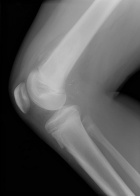

J.S. - 12 year old boy c/o right knee pain and swelling for ten days. Painful at rest, worse at night and with activity. Able to ambulate with pain. Initially the pain was accompanied by fever, chills, malaise, nausea and vomiting; all of which have resolved.